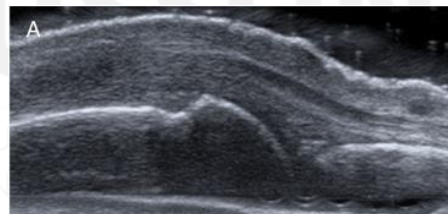

Grade this doppler

Grade 2: Larger than grade 1 + <50% of SH area